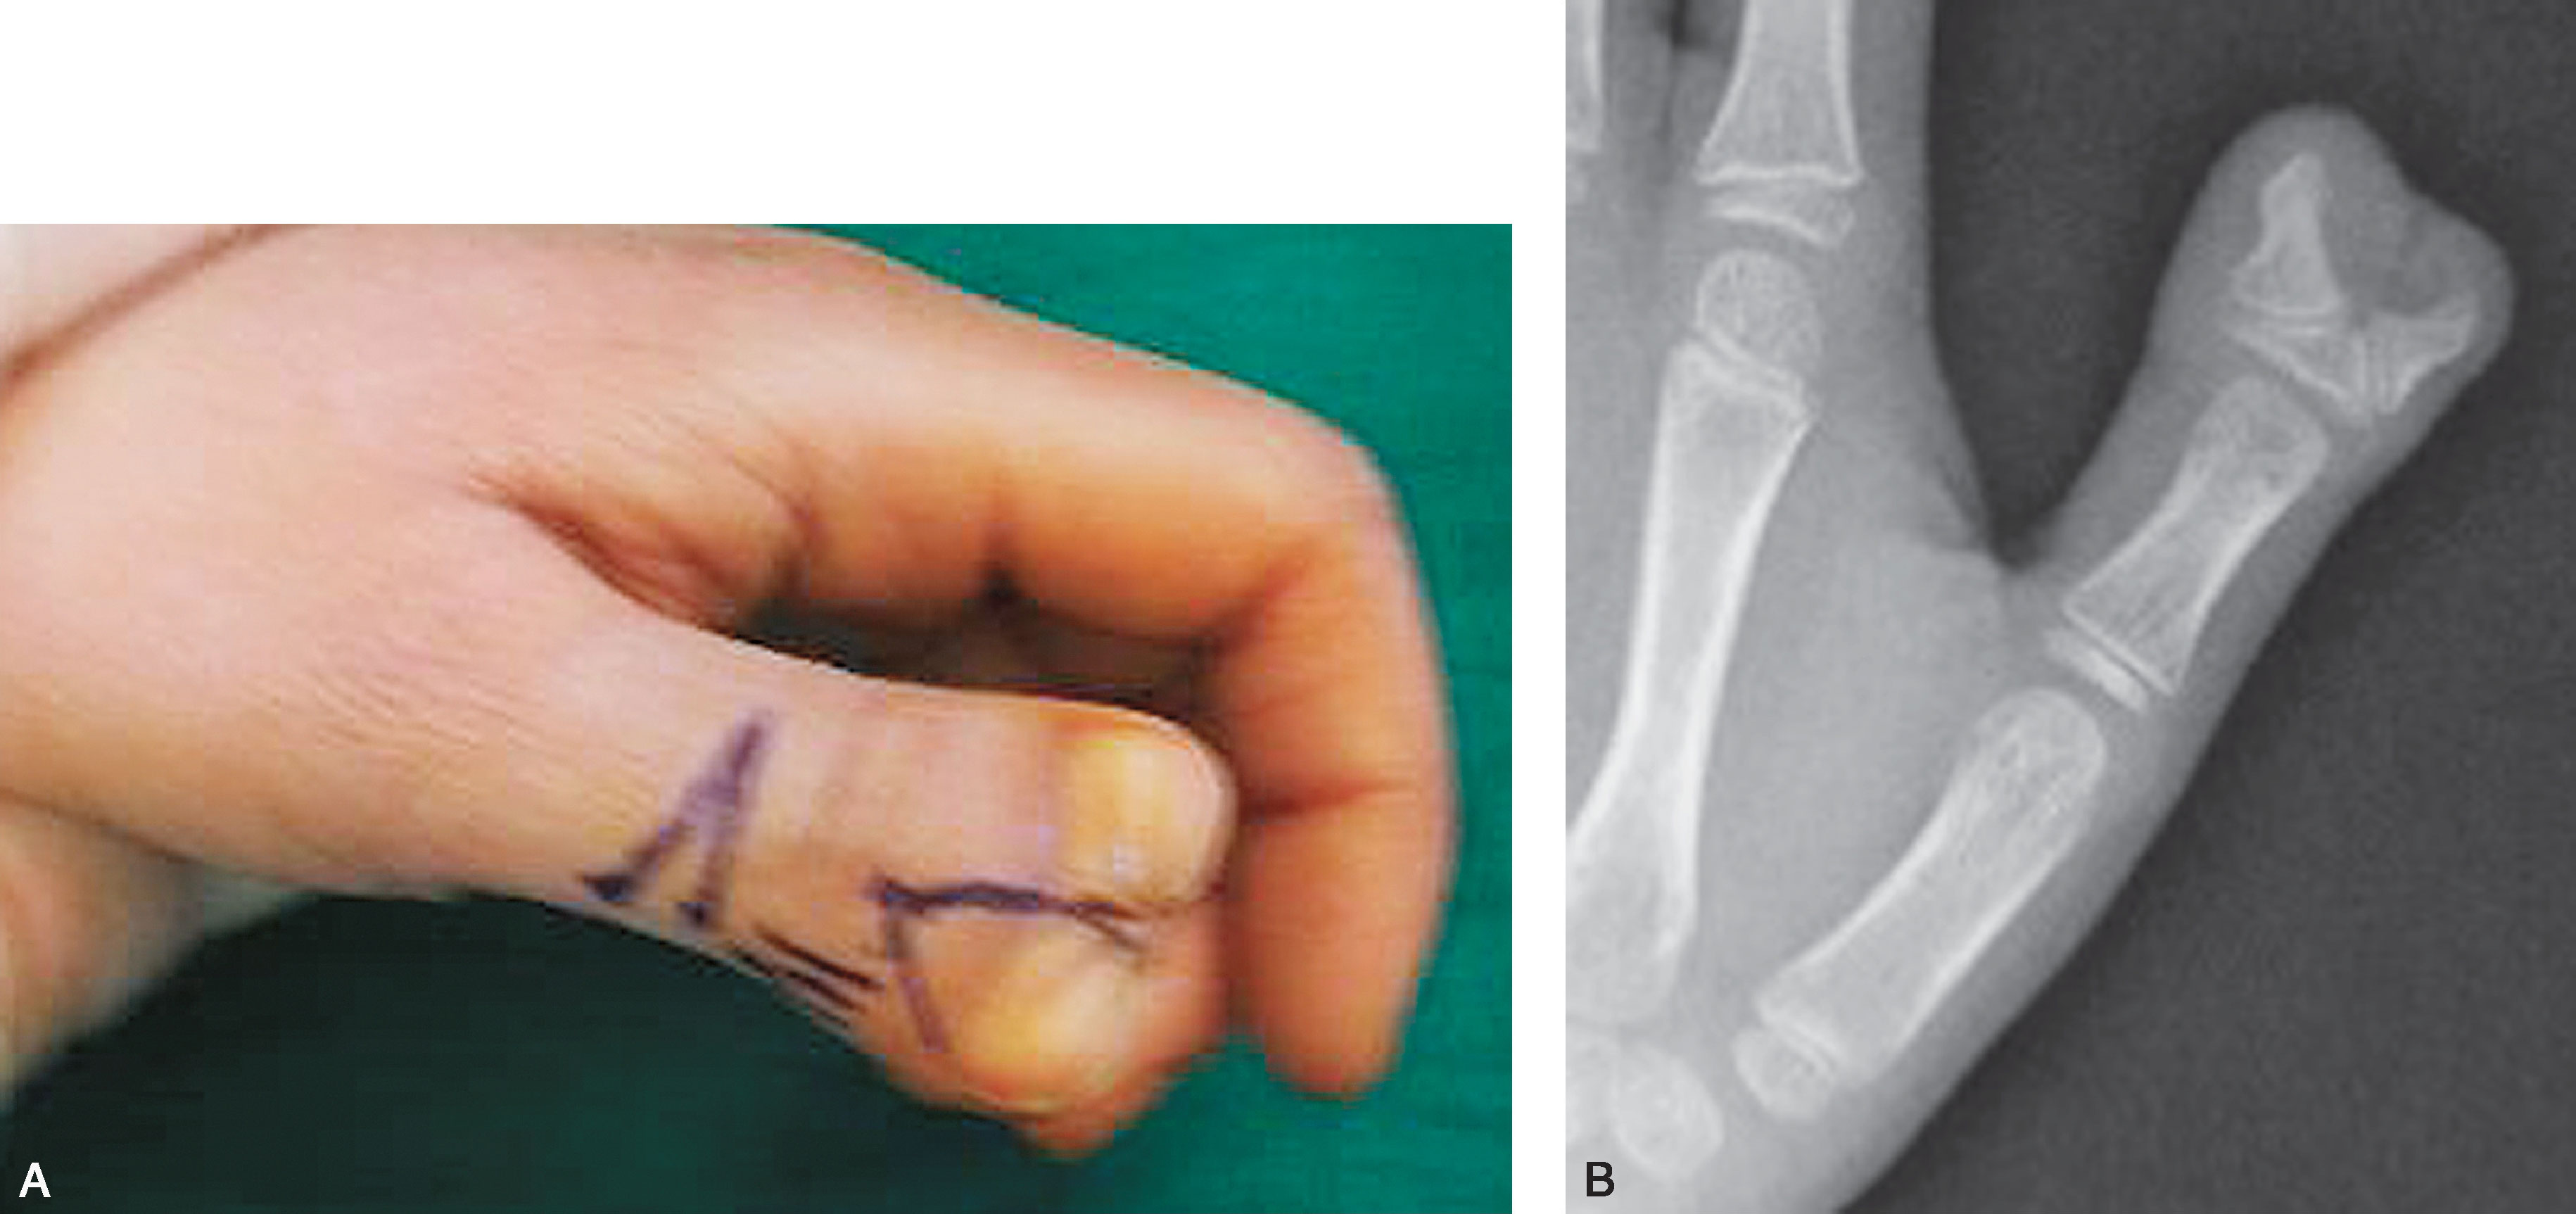

3.Ⅲ型 双末节指骨,近节指骨不完全分裂,掌骨正常(图2-1-12~图2-1-19)。

图2-1-12 Ⅲ型病例1

A.主、次拇指外形及大小接近,可以选择主、次拇指融合术式;B.X 线片显示桡侧末节指骨较小,其近端可见一个细小骨,与尺侧远节指骨难以融合为一个规整的指骨,尺侧拇指骨关节形态及力线均可,因此切除桡侧拇指保留尺侧拇指更合理